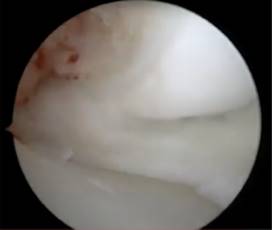

Figura 5: Visión artroscópica de la revisión de la estabilidad del cuerpo del menisco medial con gancho palpador.

Durante la artroscopía de la rodilla derecha, se encontró una lesión compleja en el menisco medial, que fue diagnosticada como un menisco discoide. Además, se observó una abundante sinovitis y Hoffitis, así como la presencia de una banda fibrosa en la parte ventromedial (Figuras 3 y 4). Se realizó una plastía del menisco medial mediante saucerización y se determinó que el menisco medial estaba estable, por lo que no se requirió el uso de suturas meniscales (Figuras 5 a 7). También se realizó la resección de la banda fibrosa, sinovectomía y Hoffectomía.